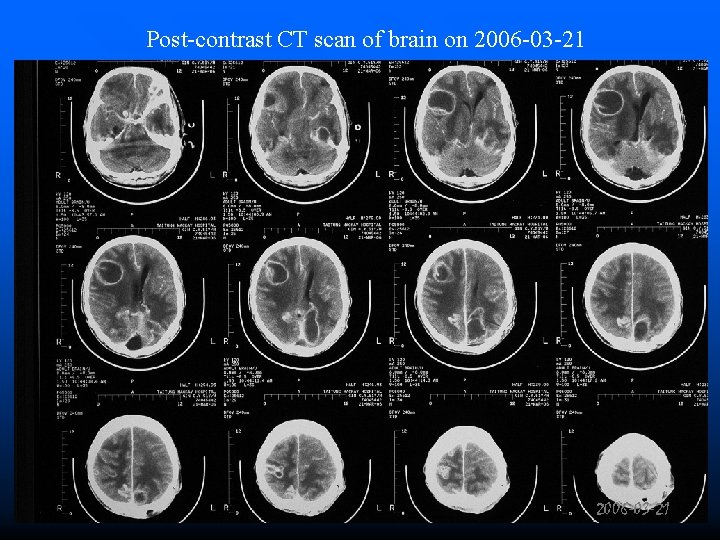

Post-contrast CT scan of brain on 2006 -03 -21

Clinical Course • 2006 -03 -06 ~ 2006 -03 -20 • 2006 -03 -20 • 2006 -03 -21 • 2006 -03 -22 • 2006 -03 -24 Fever off and on Quadriplegia GCS=4~5 WBC=7600 Hb=11. 0 BUN/Cr=12/0. 6 Na/K=144/3. 6 Brain CT Hypotension Passed away